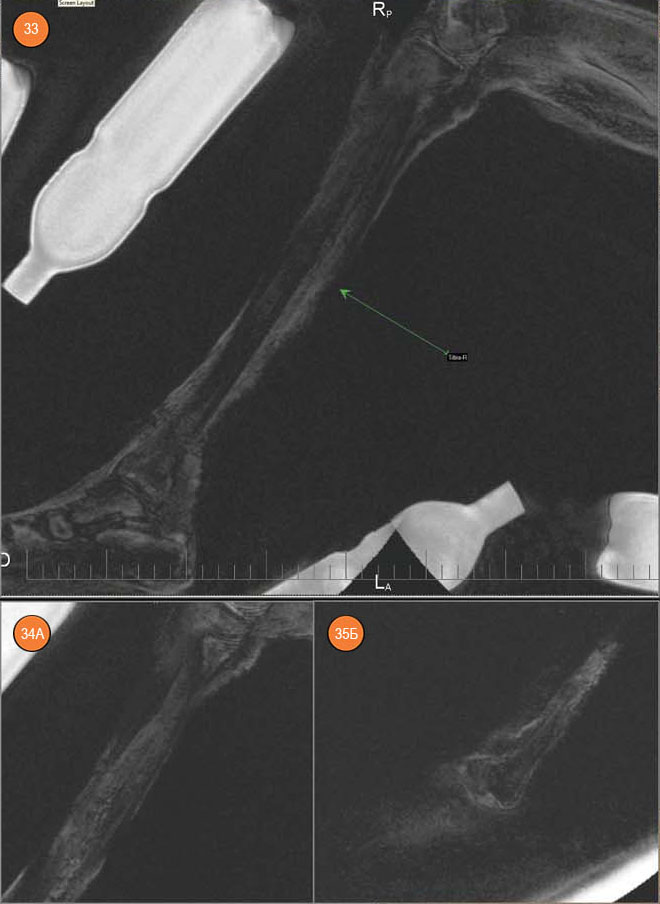

Поскольку пояс нижних конечностей у мумии при томографии находился не в ортогональной позиции, для измерения размеров малого таза пришлось использовать технологию 3D MPR.

Расстояние между большими вертелами бедренных костей оценено в 19 см, но, учитывая вывих правого тазобедренного сустава, можно говорить о том, что при жизни оно было равно 23,0–23,5 см (современная норма — 30–31 см). Расстояние между передними верхними остями подвздошных костей составило 19 см (современная норма — 25–26 см).

Поскольку измеренные наружные размеры малого таза мумии значительно отличаются от нормы, а размеры черепа ее самой и ее взрослых современников и современного человека схожи, то закономерно встает вопрос о размерах полости малого таза. Его размеры — принципиально важный вопрос для деторождения, поскольку малый таз представляет собой костную часть родового канала: его задняя стенка состоит из крестца и копчика, боковые образованы седалищными костями, а передняя — лобковыми костями и симфизом.

Рис. 23. Измерение distantia intertrochanterica. Рис. 24. Измерение distantia interspinalis. Рис. 25. Измерение поперечного размера плоскости широкой части малого таза. Рис. 26. Измерение поперечного размера плоскости выхода из малого таза

Размеры малого таза у мумии оказались гораздо меньше, чем у современных женщин. Опираясь на современные акушерские нормы, можно говорить о III степени суженности таза, при которой невозможны естественные роды (в современных условиях показано кесарево сечение). С другой стороны, нельзя полностью исключить возможность деторождения. Можно предположить эволюцию биомеханики родов, поскольку строение крестца у мумии отличается от современного: межпозвонковые диски не утрачены — по-видимому, крестцовый отдел позвоночника был достаточно подвижен и только 2–3 верхних крестцовых позвонка являли собою единый крестец. Вполне возможно, что такое строение крестца компенсировало узость родового канала. Не исключено также, что в те времена у молодых особей соединения между костями таза могли быть более подвижными, чем в наши дни, поскольку репродуктивный возраст начинался у них уже в начале второго десятилетия жизни при ее средней продолжительности в 30–40 лет. Более того, в условиях относительно ограниченных пищевых ресурсов рождение крупного потомства было маловероятным.